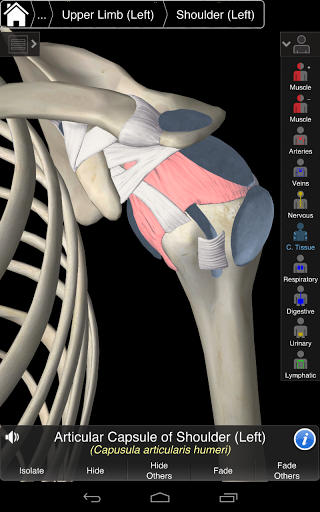

Essential Anatomy 3 representa lo último en tecnología 3D innovadora y diseño innovador. Un motor de gráficos 3D de vanguardia, creado a medida por 3D4Medical desde cero, alimenta un modelo anatómico altamente detallado y ofrece gráficos de calidad excepcional que ningún otro competidor puede lograr.

La aplicación representa un enfoque único para el aprendizaje de la anatomía general. Los gráficos no tienen paralelo y hacen que el aprendizaje, a través del uso de contenido informativo y características innovadoras, sea una experiencia rica e interesante.

NUEVA TECNOLOGÍA 3D

Essential Anatomy 3 es receptivo, visualmente impactante y sin esfuerzo. La aplicación es totalmente en 3D, lo que significa que puedes ver cualquier estructura anatómica de forma aislada y desde cualquier ángulo.

Essential Anatomy 3 está diseñado pensando en el usuario: el cuerpo mismo se convierte en la interfaz. A diferencia de otras aplicaciones 3D, que se basan en arreglos anatómicos predefinidos y disecciones regionales para guiar al usuario, Essential Anatomy 3 de 3D4Medical le permite encontrar lo que está buscando sin complicaciones.

---- Más de 4,000 estructuras anatómicas altamente detalladas

---- Nomenclatura latina para cada estructura anatómica